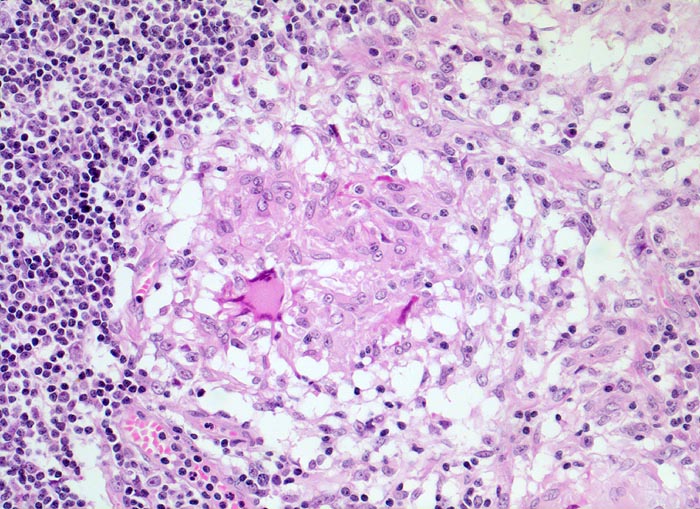

• Girlandenförmige basophile Nekrosezonen durchsetzt von neutrophilen Granulozyten (abszedierende Entzündung).

• Demarkierung der Abszesse durch palisadenförmig angeordnete epitheloide Histiozyten (heller Randwall um die Abszesse).

• Vereinzelt mehrkernige Riesenzellen im histiozytären Randwall.